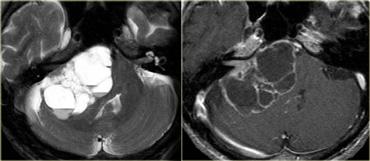

U thần kinh bao (Schwannoma) vùng góc cầu tiểu não với các đặc điểm điển hình của u ngoài trục (Chuỗi xung T2W)

Chuỗi xung T2W cho thấy một u thần kinh bao (schwannoma) nằm ở góc cầu tiểu não (CPA).

Trường hợp này minh họa rõ nét các dấu hiệu điển hình của u ngoài trục.

Có khe dịch não tủy (mũi tên vàng).

Các mạch máu dưới nhện chạy trên bề mặt não bị tổn thương đẩy lệch (mũi tên xanh lam).

Có chất xám nằm giữa tổn thương và chất trắng (mũi tên đỏ cong).

Khoang dưới nhện bị giãn rộng do sự phát triển của tổn thương ngoài trục có xu hướng đẩy lùi não.

Tất cả các dấu hiệu này cho thấy đây là một u ngoài trục điển hình.

Tại vùng góc cầu tiểu não, 90% các u ngoài trục là u thần kinh bao (schwannoma).